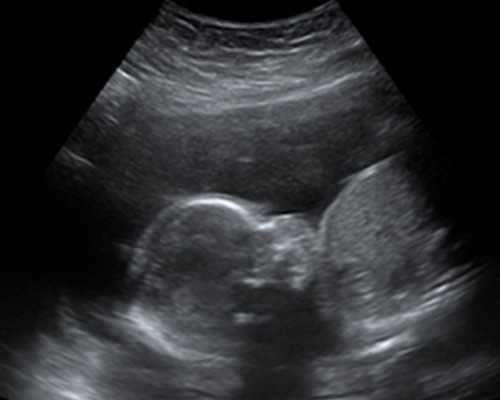

武汉有的许多怀孕援助机构和公医院。到2024年,共有13家医疗机构将获得辅助生殖技术许可。比如能开展一代和第二代试管婴儿技术的医院就多达8家,包括武汉同济医院、武汉协和医院、武汉大学人民医院、湖北省妇幼中心、中科大生殖医学中心等。为了让更多的姐妹更容易知道武汉哪些助孕机构好,根据排名前十的试管婴儿医院等信息,介绍具体的助孕机构和公司。